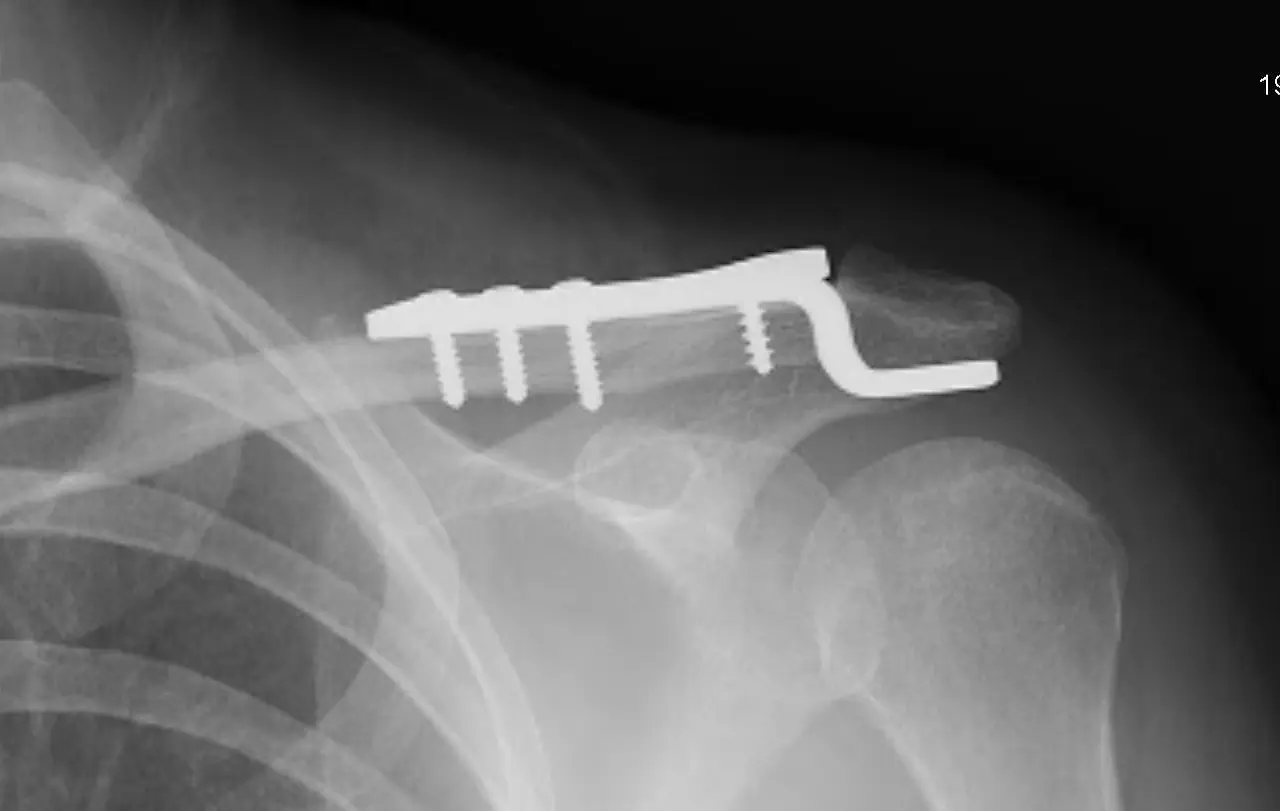

** 이 포스트에는 금속 후크 플레이트 수술에 관한 참고용 엑스레이 자료가 게재되어 보시기에 다소 불편하실 수 있습니다.

의사는 나의 골절된 위치가 어깨관절로 연결되는 쇄골의 끝쪽이라 통상적으로는 수술을 해야한다고 했다. 그러나 내 뼈의 어긋난 상태가 현재로선 수술하기는 아깝단다. 참고로 여기서 수술이란 전신마취 상태로 어깨에 후크플레이트라는 금속판을 박는 수술. ㅠㅠ 진료를 보던 의사가 굳이 내게 다른 사람의 수술 후의 엑스레이를 보여주었다. 너무 무서웠다. (아래 사진은 내가 검색으로 찾아본 후크플레이트 수술에 관한 참고용 자료이다.)

후크 플레이트를 적용한 쇄골 수술

엑스레이 사진 출처

Distal Third Clavicle Fractures, Evan Watts